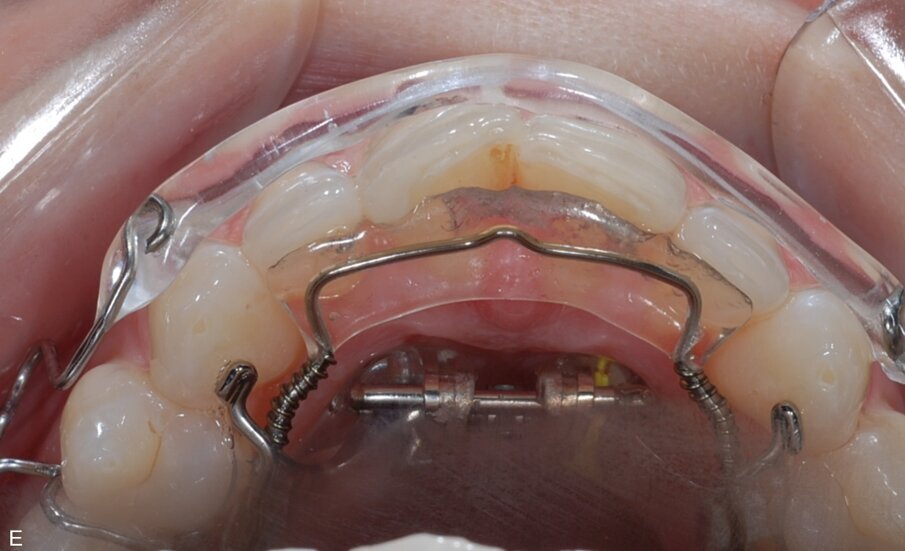

Fig. 9: ClearSmile Inman Aligner fitted

At the initial appointment, palatal anchors were placed, with interproximal reduction (IPR) and predictive proximal reduction (PPR) carried out using the guide issued from the laboratory. The patient was instructed on how to turn the expander. Aligner in situ. At the initial appointment, palatal anchors were placed, with interproximal reduction (IPR) and predictive proximal reduction (PPR) carried out using the guide issued from the laboratory. The patient was instructed on how to turn the expander. Aligner in situ. |